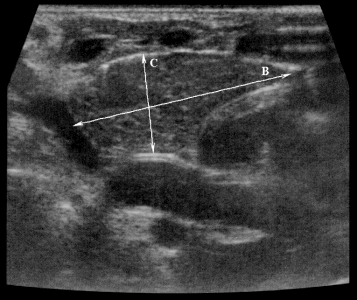

| Фото. На продольном срезе правой (А) и левой доли (В) измеряют длину и толщину (передне-задний размер), а на поперечном срезе (Б) — ширину долей. | ||